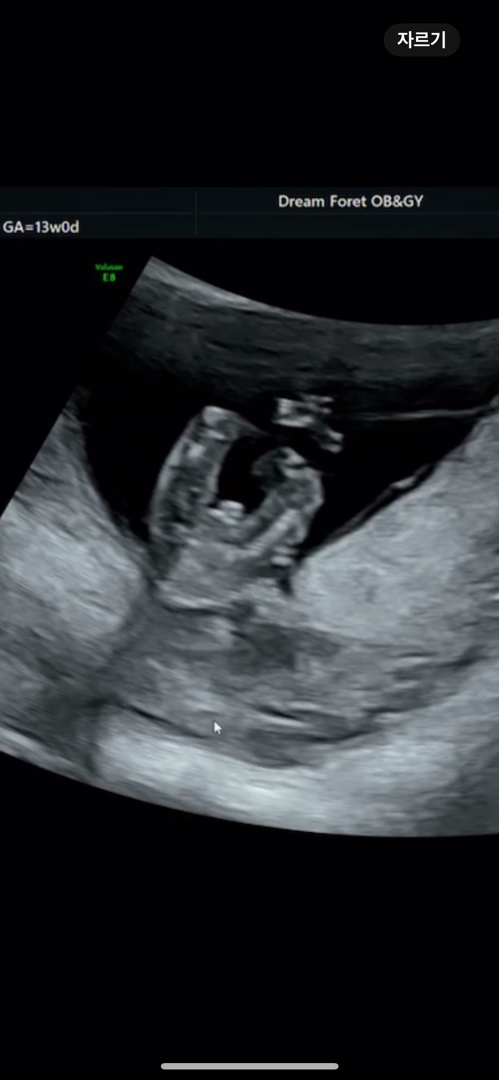

13주 엉덩이사진인데 성별 어떻게 보이시나요..? 🩵

선생님은 뚜렸하게 말씀 안해주시는데... 어떤 성별 같이 보이시나요...?